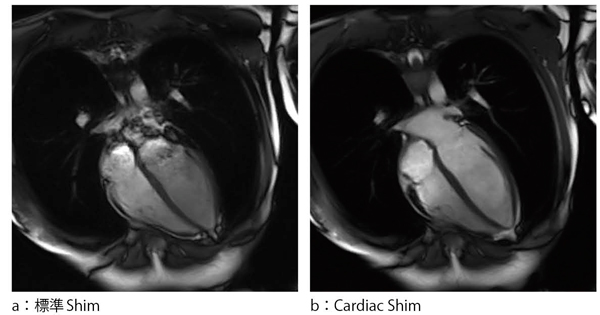

胸部では,肺(空気)と実質の境界にある磁気感受率の差により磁場の不均一が生じる。磁気感受率の影響は静磁場強度に比例するため,3.0Tにおいて顕著に発現し,磁場の不均一の補正は必須となる。通常,被検者が入ることによって生じる磁場の不均一は,すべての検査においてアクティブシムにより被検者ごとに調整される。シーメンスでは,心臓検査においては関心領域を指定することにより,より限局して磁場の均一性を最適化するモード,Cardiac Shimを準備している(図1)。また,撮像時間が短いこと,SNに優れることなどからTrueFISP(SSFP)をベースとしたシーケンスが多用されているが,このシーケンスは磁場の不均一にきわめて鋭敏である。このため特有のバンディングアーチファクトが生じることがあるが,このアーチファクトが関心領域にかからないように共鳴周波数をわずかに変化させることにより,その位置をずらす必要がある。Frequency Scoutでは,複数の周波数差を持つ画像を事前に撮像し,被検者ごとに異なる周波数差を容易に検索することが可能となっている。

図1 標準ShimとCardiac Shim後の画像比較(TrueFISP) 心臓検査に特化したCardiac Shim(b)では心腔内がより均一に描出されている。

心臓検査に特化したCardiac Shim(b)では心腔内がより均一に描出されている。